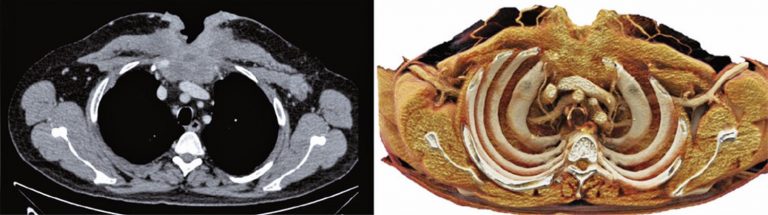

DOI: 10.31744/einstein_journal/2020MD5223

RESUMO A tomografia computadorizada com os múltiplos detectores e o avanço dos processadores melhoraram as imagens renderizadas e as reconstruções tridimensionais na prática clínica. Os cortes axiais tradicionais formam imagens não intuitivas, pois são vistas em apenas um plano. Já as reconstruções tridimensionais podem exibir detalhes anatômicos em diferentes perspectivas das estruturas e de doenças com anatomia complexa. A renderização cinematográfica é uma técnica de reconstrução tridimensional recentemente introduzida, já aprovada para uso clínico, que pode produzir imagens realistas a […]

Palavras-chave: Imagem tridimensional; Processamento de imagem assistida por computador; Tomografia computadorizada por raios X